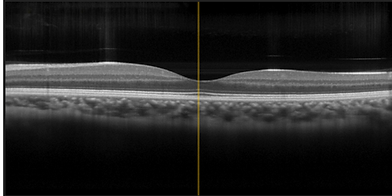

Optical coherence tomography OCT

Digital retinal imaging DRI